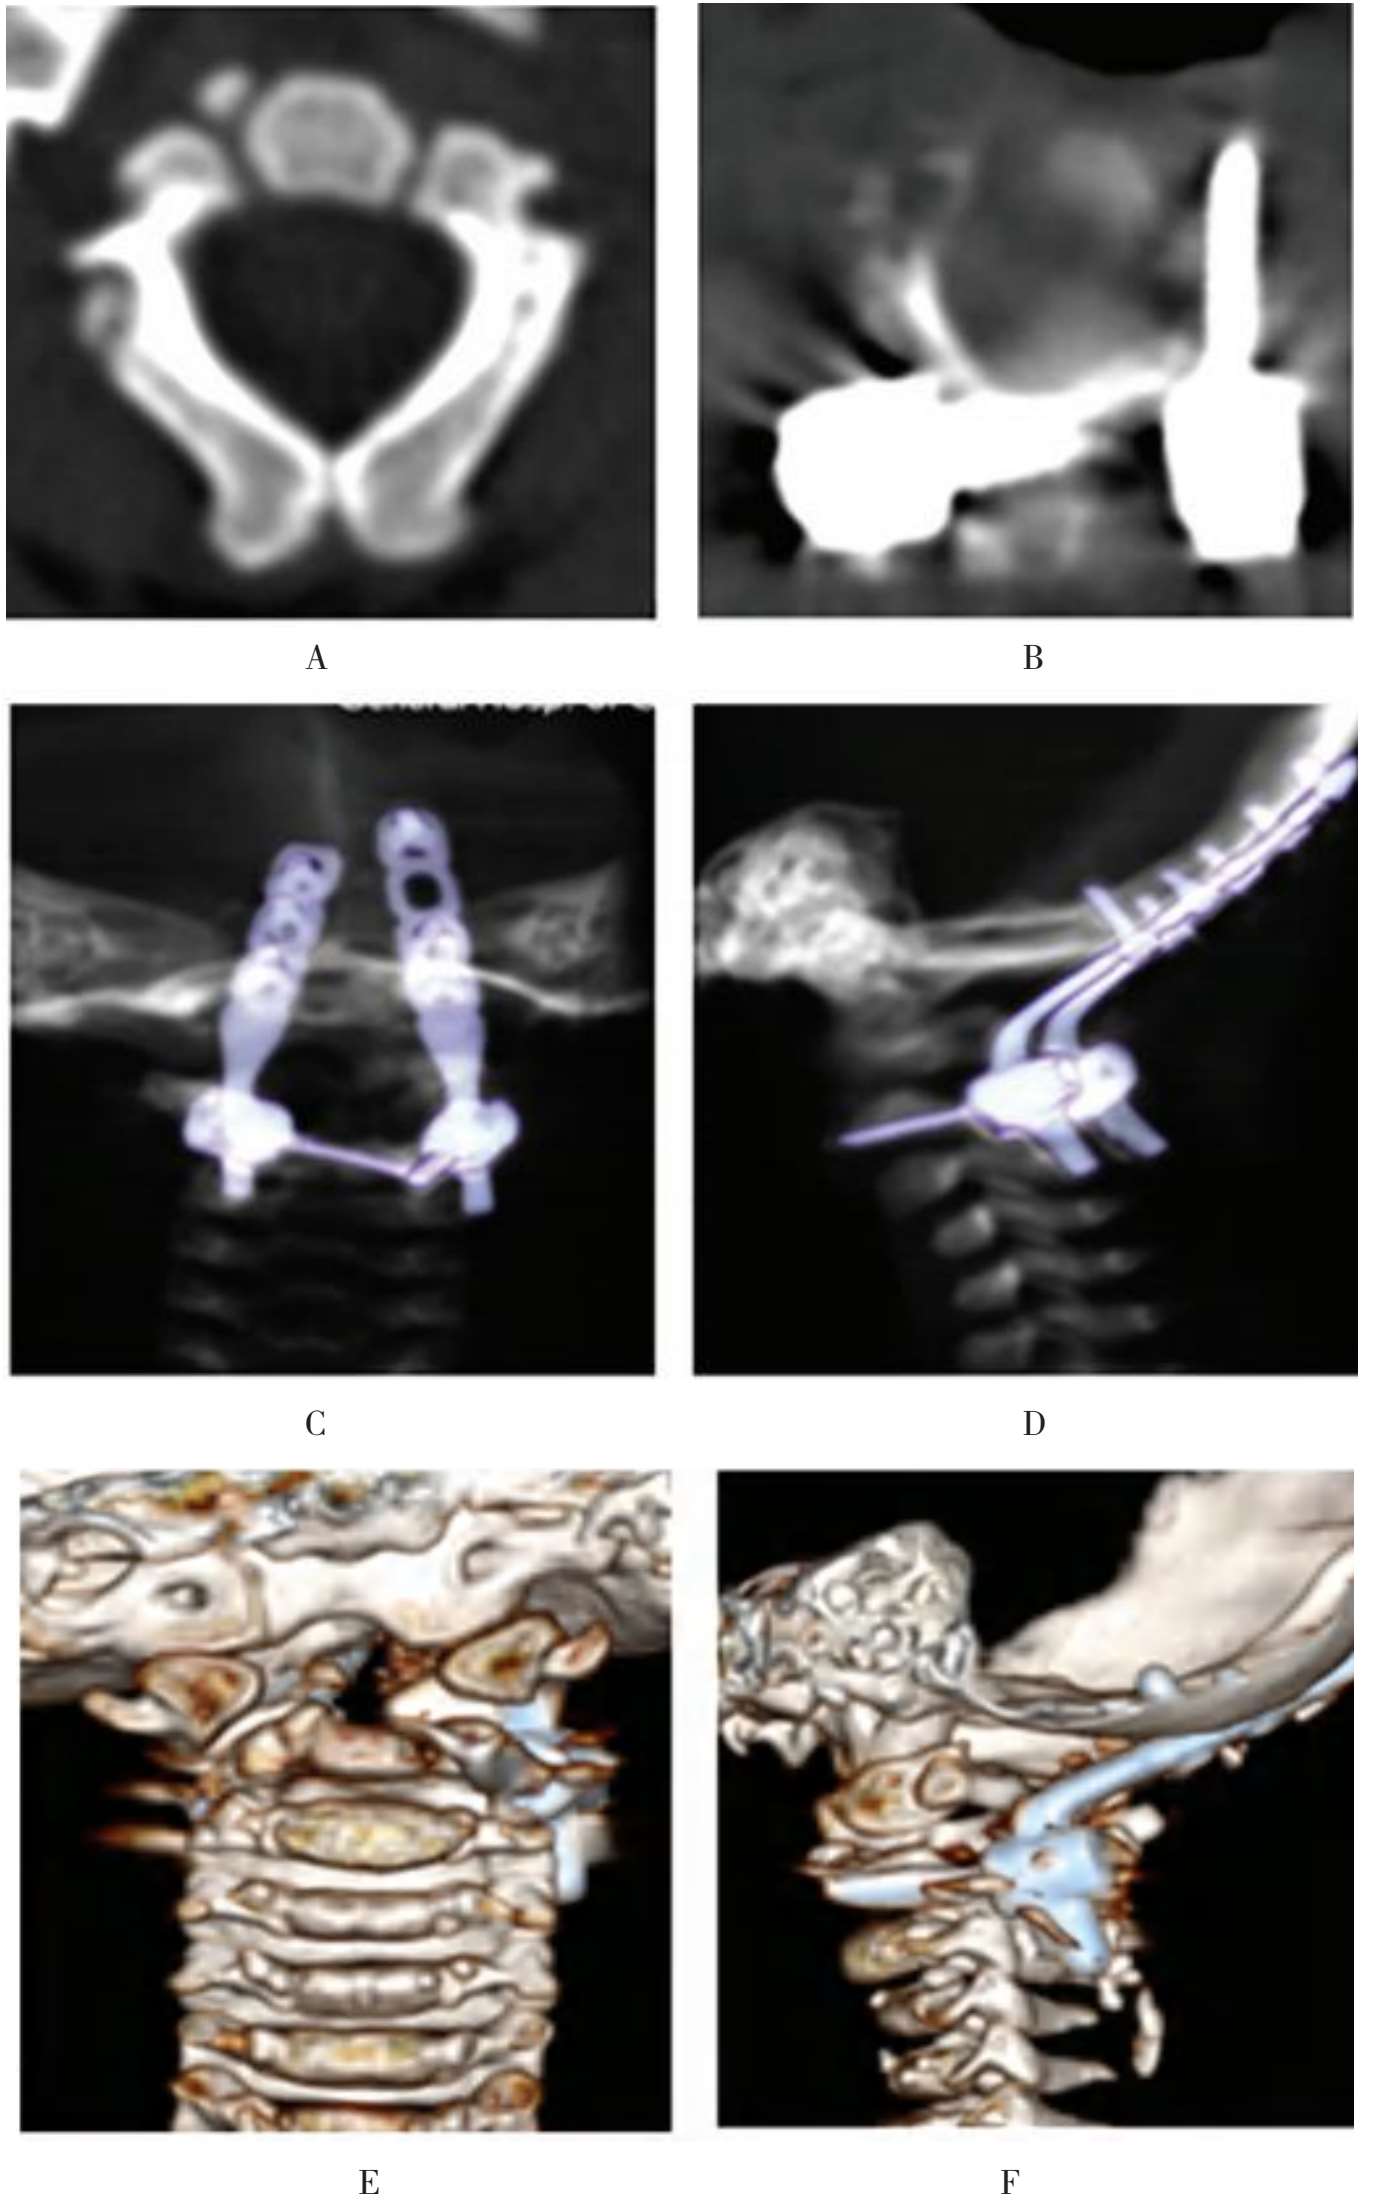

患儿的颈椎CT检查提示多发性枕颈交界区畸形:①C 1 前后弓发育不良;②齿状突缺如;③寰枢椎脱位(图1-28)。

A~D.术前CT示颅颈椎交界区多发畸形

图1-28 典型病例介绍

术后影像学检查示寰枢椎脱位获得理想复位,内固定位置良好(图1-30、图1-31)。

A~F.患儿接受后路寰枢椎复位,枕颈椎固定融合手术

图1-30 典型病例介绍

A.术前;B.术后

图1-31 典型病例介绍,术前、术后核磁共振对比,患儿脊髓压迫解除